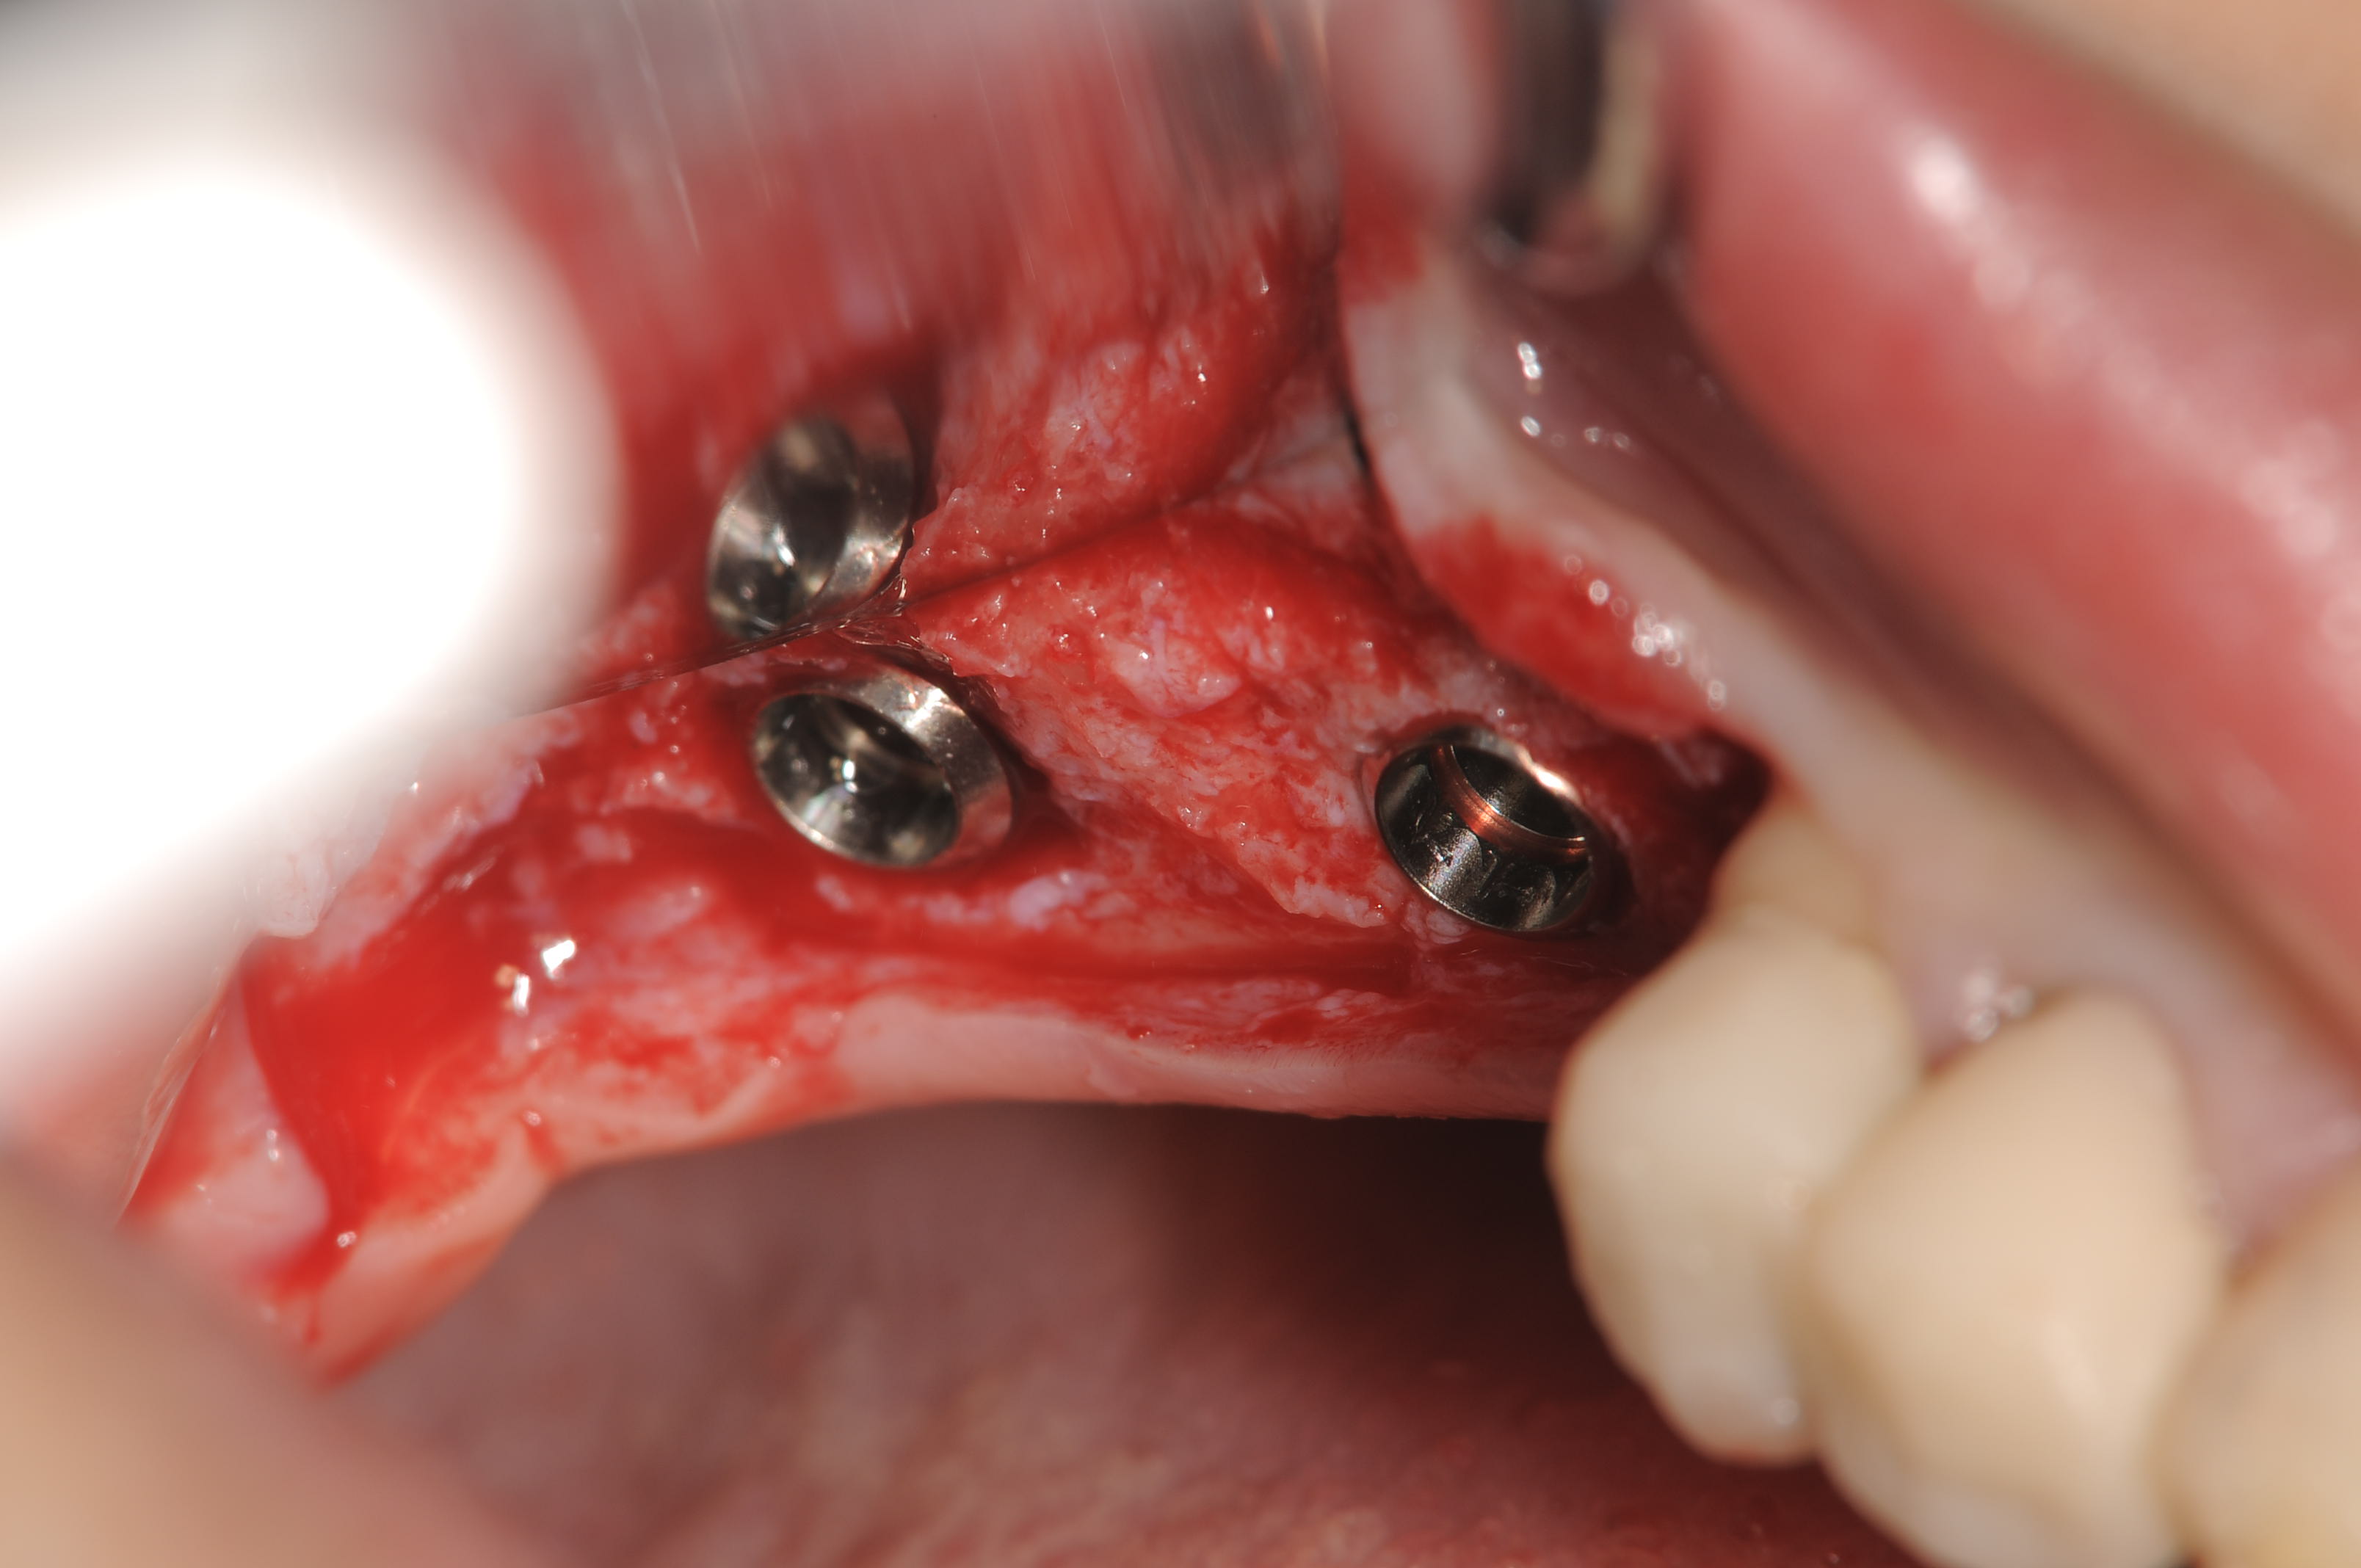

今日2度目のオペは、下顎67欠損部位の抜歯早期埋入で、サイブロンプロEXを使用しました。

RN4.1Φ9mmを2本、やや骨縁下へ埋入し、プラットフォームシフト用のヒーリングアバットメントを装着して1回法としました。

固定も十分ですので、3か月で上部構造の製作に移行していきます。

パラレルピンで平行性を必ず確認します。

やや骨縁下に埋入しました。

理想的な埋入深度が得られたと思います。